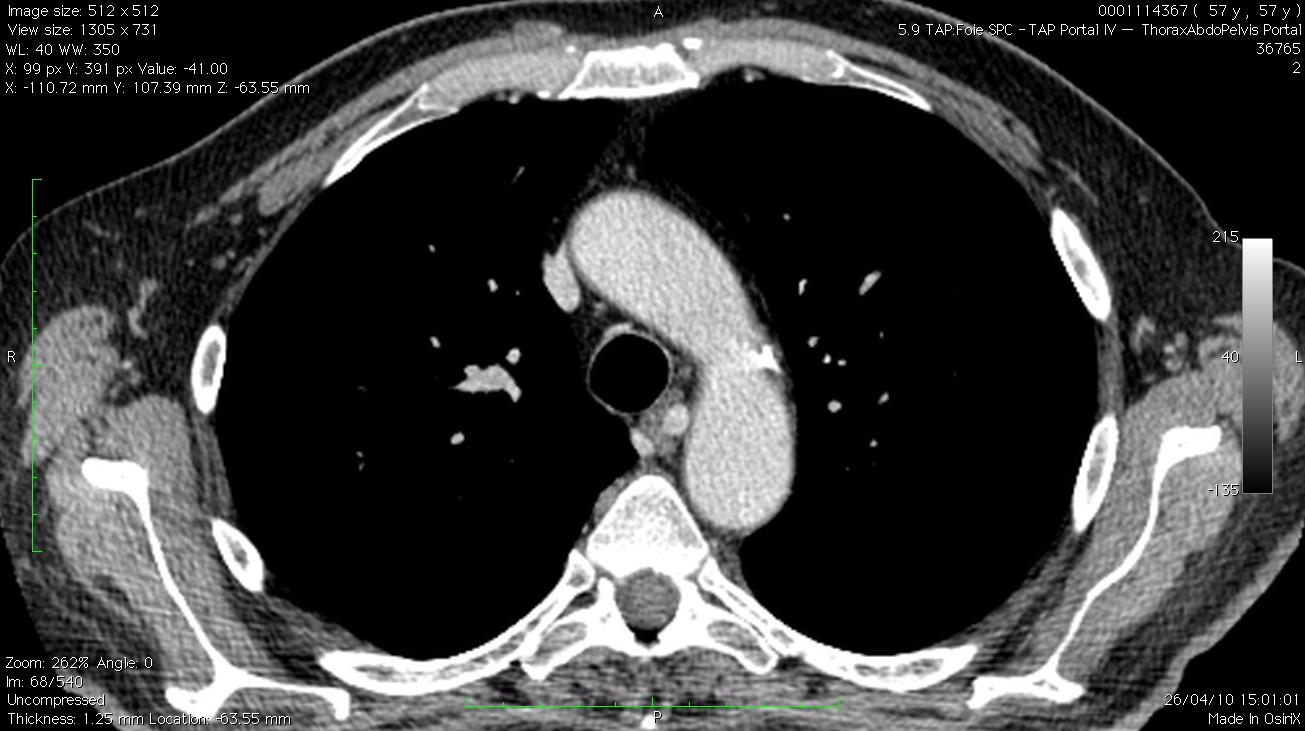

En regardant le scanner avec le radiologue, il s’agit en fait une artère bronchique ectasique naissant de la face postérieure de la crosse. Cette dilatation est elle en rapport avec l’EP massive survenue quelques mois plus tôt??? (La collatéralité par des artères bronchiques sur des EP importantes a déjà été décrite)